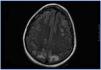

En el período interdiálisis presenta malestar general, desorientación temporal y nivel de conciencia fluctuante. Es trasladada al Servicio de Urgencias, donde presenta dos crisis convulsivas tónico-clónicas generalizadas, que ceden con benzodiazepinas, con recuperación del nivel de conciencia entre las crisis. En la exploración física se muestra afebril, con tensión arterial (TA): 151/108, apertura ocular espontánea, respuesta verbal correcta. Pupilas isocóricas y normorreactivas. Pares craneales normales; fuerza y sensibilidad conservada en las cuatro extremidades. Signos meníngeos negativos. No presenta otros hallazgos de interés. Se realiza radiografía de tórax y tomografía computarizada craneal, sin hallazgos. Ante una tercera crisis y el empeoramiento progresivo de su estado general, ingresa en la Unidad de Cuidados Intensivos, donde precisa sedación, intubación orotraqueal y ventilación mecánica inducida (VMI). En la analítica destaca leucocitosis con desviación izquierda, acidosis láctica severa, negatividad de anticuerpos antimembrana basal, anticuerpos antinucleares, anticuerpos anticitoplásmicos de neutrófilos, inmunocomplejos, anti-DNA, anti-SS-A. anti-SS-B, anti-RNP, anti-Scl-70, con complemento e inmunoglobulinas normales. Hemocultivos y urocultivos negativos. Estabilidad iónica. Fibrobroncoscopia sin hallazgos. Punción lumbar normal. Cultivo de líquido cefalorraquídeo para bacterias, hongos y virus negativo. Electroencefalograma con ritmo basal lento en rango delta con ondas de actividad theta de predominio en regiones temporales bilaterales. Dos descargas epileptiformes en zona parietal derecha. Resonancia magnética nuclear (RMN) craneal con hiperintensidad de señal en secuencias potenciadas en T2 y FLAIR, sugerente de edema vasogénico, de localización corticosubcortical en las porciones posteriores de ambos lóbulos parietales, occipitales y frontal derecho que en la secuencia de difusión no muestra restricción significativa (figura 1). Ante estos hallazgos, se llega al diagnóstico de SLPR. Se inicia tratamiento con fenitoína, antibioterapia empírica y hemodiafiltración venovenosa continua. Mantiene severa HTA que precisa tratamiento con 6 fármacos (captopril, amlodipino, doxazosina, atenolol, nitroglicerina y urapidilo). En los siguientes días, mejora, sin recurrencia de las crisis y manteniendo TA correctas, por lo que se puede retirar la VMI y puede ser dada de alta a los 18 días de ingreso, con atenolol y captopril como tratamiento de base.

Figura 1. Resonancia magnética nuclear craneal